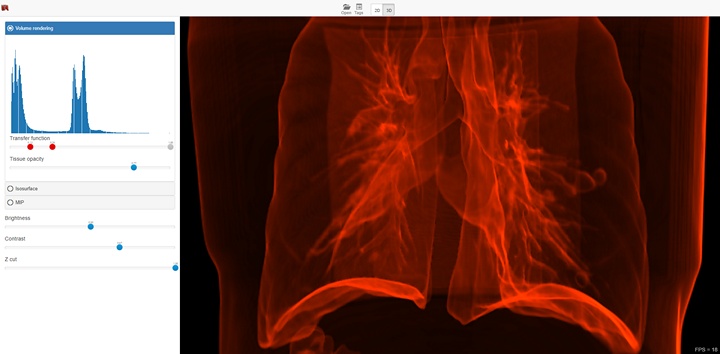

The functionality depends on the selected visualization mode (2D or 3D), and in case of 3D mode on the selected visualization method. The screenshot below shows a 3D visualization mode with a volume render method. In this case, the interface provides the ability to select areas of interest inside the volume, brightness and contrast adjustment, as well as the ability to use the near clipping plane position.

Volume Visualization¶

This method suits for studying the initial data volume and the soft tissues visualization. It allows to choose an area of the interest by specifying the transfer function, which assigns the amount of the initial data to the amount of the transparency and color. To simplify the transfer function, the user uses a function in the application. The user can define this function by adjusting three parameters (a, b, and c) with sliders. The function is nonzero only if the intensity i satisfies the conditions a < i < b or i > c. When the function satisfies the first condition, the user can determine the transparency value by the value of the additional slider, and when it satisfies the second one, the transparency value is considered equal to 1. Such a subset of transfer functions is sufficient to visualize the overwhelming array of medical data. The base of this method is the calculation of the volume integral along the rays passing through the pixels.